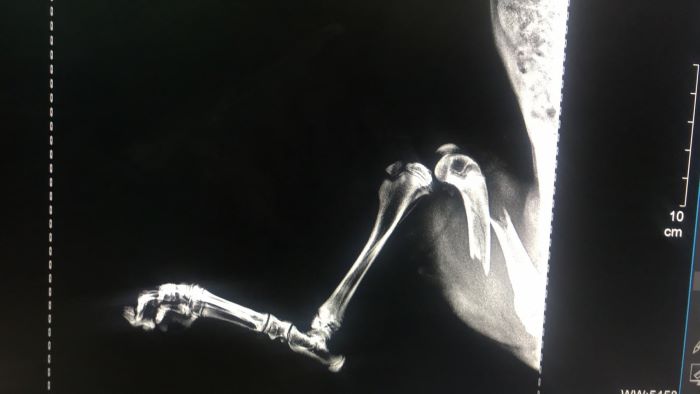

Поняла, что дело плохо. Долго искать не пришлось, щенок лежал под бетонной плитой. Не сразу поняла, что с ним. Крови не было, внешне целый. Когда попыталась его вытащить, тогда и поняла, что его задняя лапа висит как плеть. Срочно повезла в ветклинику, малыш плакал всю дорогу и продолжает до сих пор, - рассказывает Наталья Филиппова. - В клинике сделали рентген, и он показал сложный перелом с защемлением. Ортопеда не было на месте, нас отправили домой, сказали приехать на следующий день и сообщили, что операция будет стоить примерно 18 000 рублей, возможно, потребуется не одна операция. Я впала в ступор, не понимаю, из чего складываются подобного рода суммы за операцию, но малышу больно, и он хочет жить. А значит, ему нужно поскорее помочь.